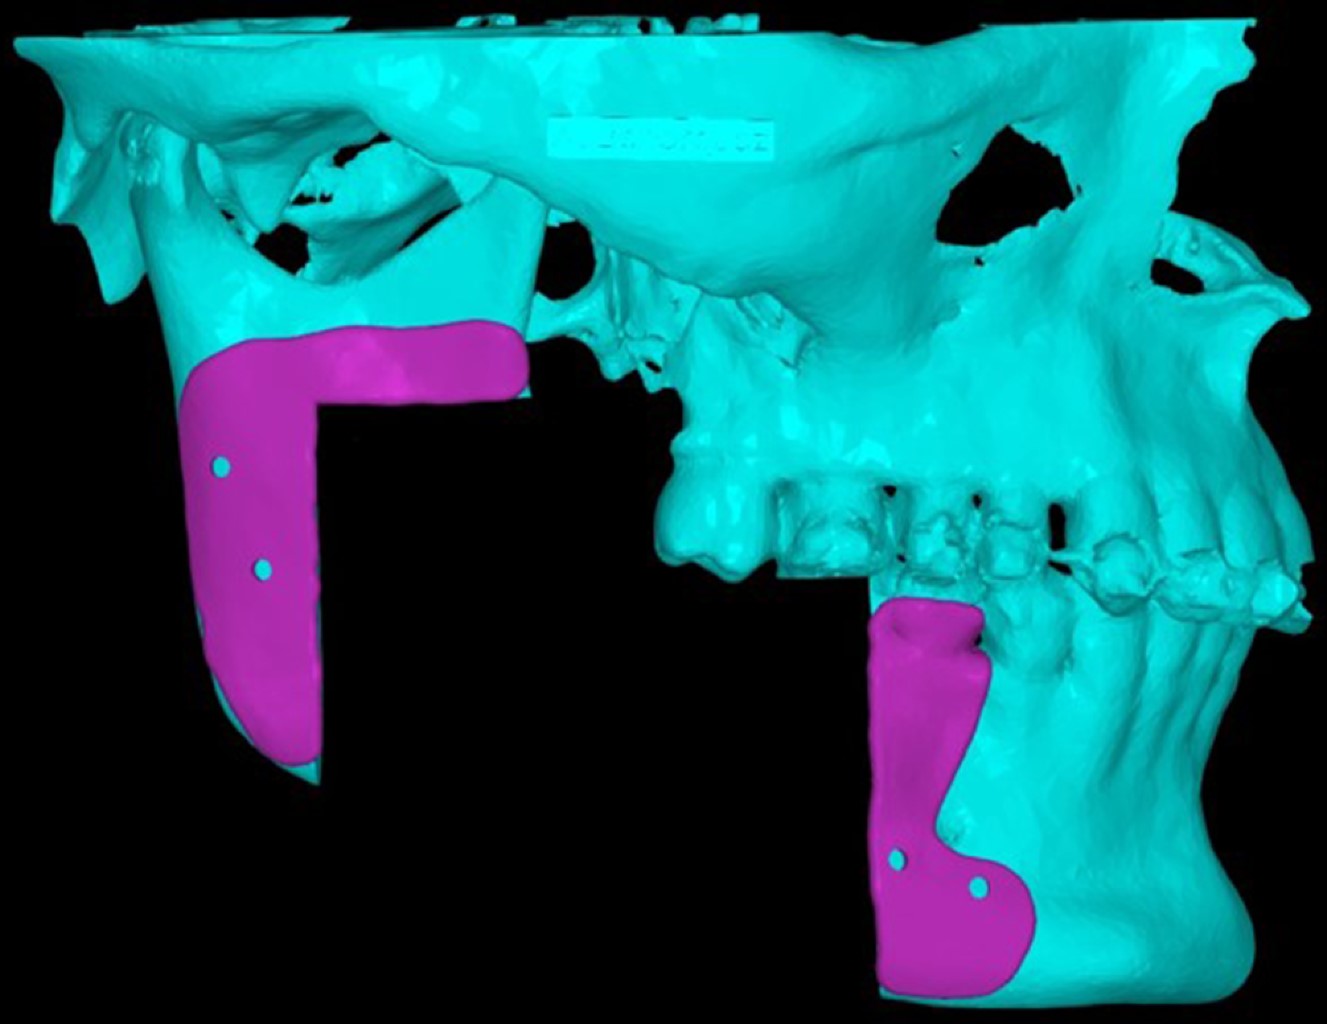

La razón fundamental para el desarrollo y el uso de la planificación quirúrgica virtual (PQV) es optimizar la capacidad del cirujano para prepararse y mitigar posibles contratiempos en el quirófano. En la literatura se encuentra relativamente poca evidencia sobre la aplicación de la PQV en procedimientos quirúrgicos complejos, aún más escasa en la literatura se refleja la bondad que ofrece la PQV en cuanto a la elección del abordaje quirúrgico. Este estudio presenta el abordaje de una lesión benigna mandibular extensa y su reconstrucción con material de osteosíntesis. Todo ello asistido por un software virtual de planificación quirúrgica que permitió realizar la ejecución virtual de la cirugía, la planificación del abordaje más conveniente para la extirpación de la lesión mediante guías quirúrgicas y la posterior reconstrucción. Enfatizando el análisis de los beneficios de la PQV y su influencia en la elección del abordaje quirúrgico más ideal y menos invasivo para el caso.

Figura 1